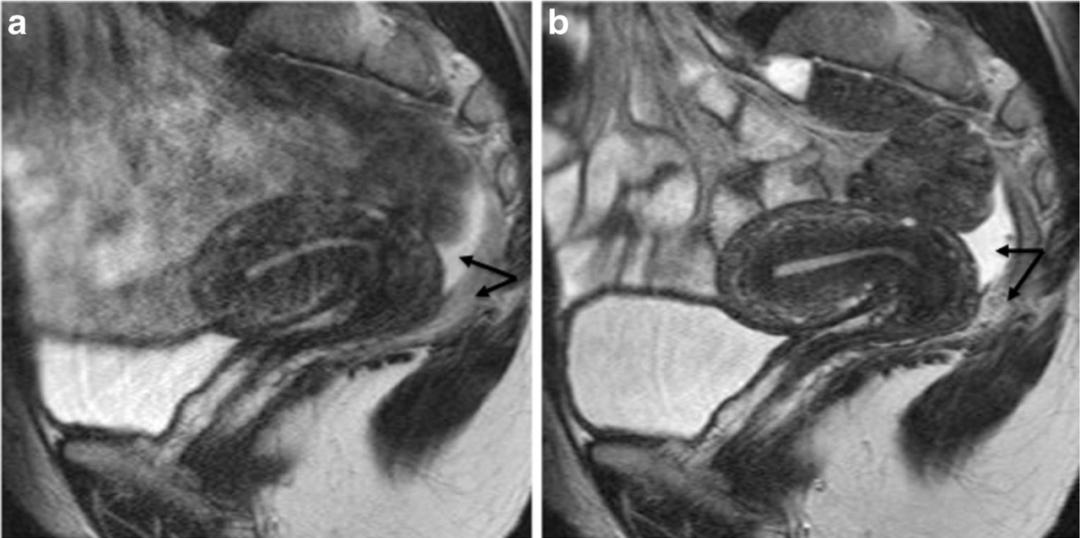

子宫内膜异位至左侧输尿管下段,T2WI 轴位和矢状位子宫颈左旁结节样低信号,边缘呈不规则星芒状,左侧输尿管扩张。

子宫内膜异位至直肠系膜,T2WI 轴位阴道左后方低信号结节,边缘星芒状,累及直肠系膜,但未累及直肠壁。